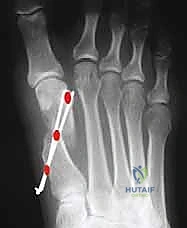

توضح هذه الصورة مدى الانحراف الشديد في مفصل إبهام القدم، وهو ما يستدعي تدخلاً جراحياً متقدماً مثل جراحة شفرون الممتدة لضمان عدم الانتكاس.

في حالة ورم إبهام القدم الأروح، ينزلق العظم المشطي الأول عن هذه العظام السمسمانية (Subluxation)، مما يعطل الميكانيكا الطبيعية للمفصل ويؤدي إلى تآكل الغضاريف والألم الشديد. الهدف الأساسي للأستاذ الدكتور محمد هطيف في الجراحة هو إعادة العظم المشطي ليستقر تماماً فوق هذه العظام السمسمانية.

يظهر هنا كيف يؤدي انحراف العظم المشطي إلى خروج العظام السمسمانية عن مسارها الطبيعي، مما يسبب ألماً مبرحاً أسفل القدم ويستدعي تحريراً دقيقاً للأنسجة الرخوة أثناء الجراحة.

تُظهر الصورة كيف يتم دفع رأس العظم المشطي إلى مكانه التشريحي الصحيح، مما يقضي على الزاوية المرضية ويعيد للقدم استقامتها.